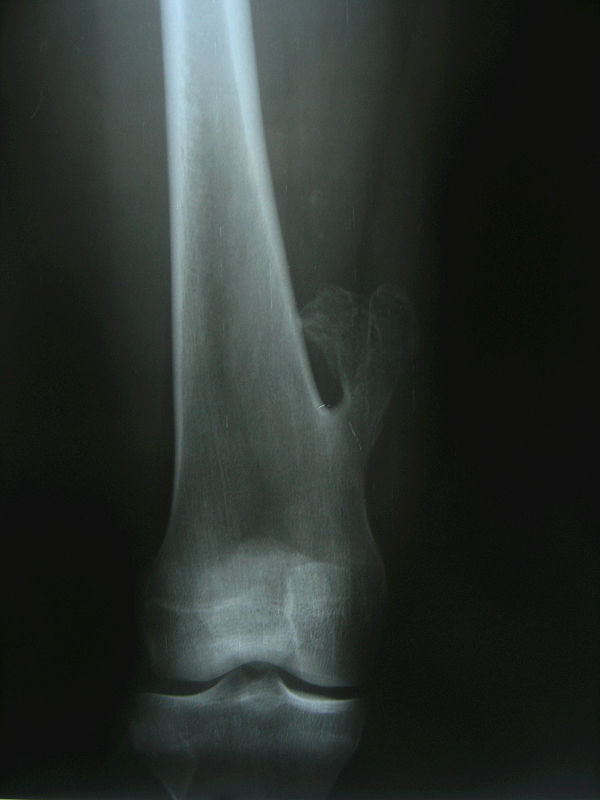

2.病例2: 男 14岁 多发性骨软骨瘤

图 8 双胫骨近端病灶(正位)

图 9 双胫骨近端病灶(侧位)